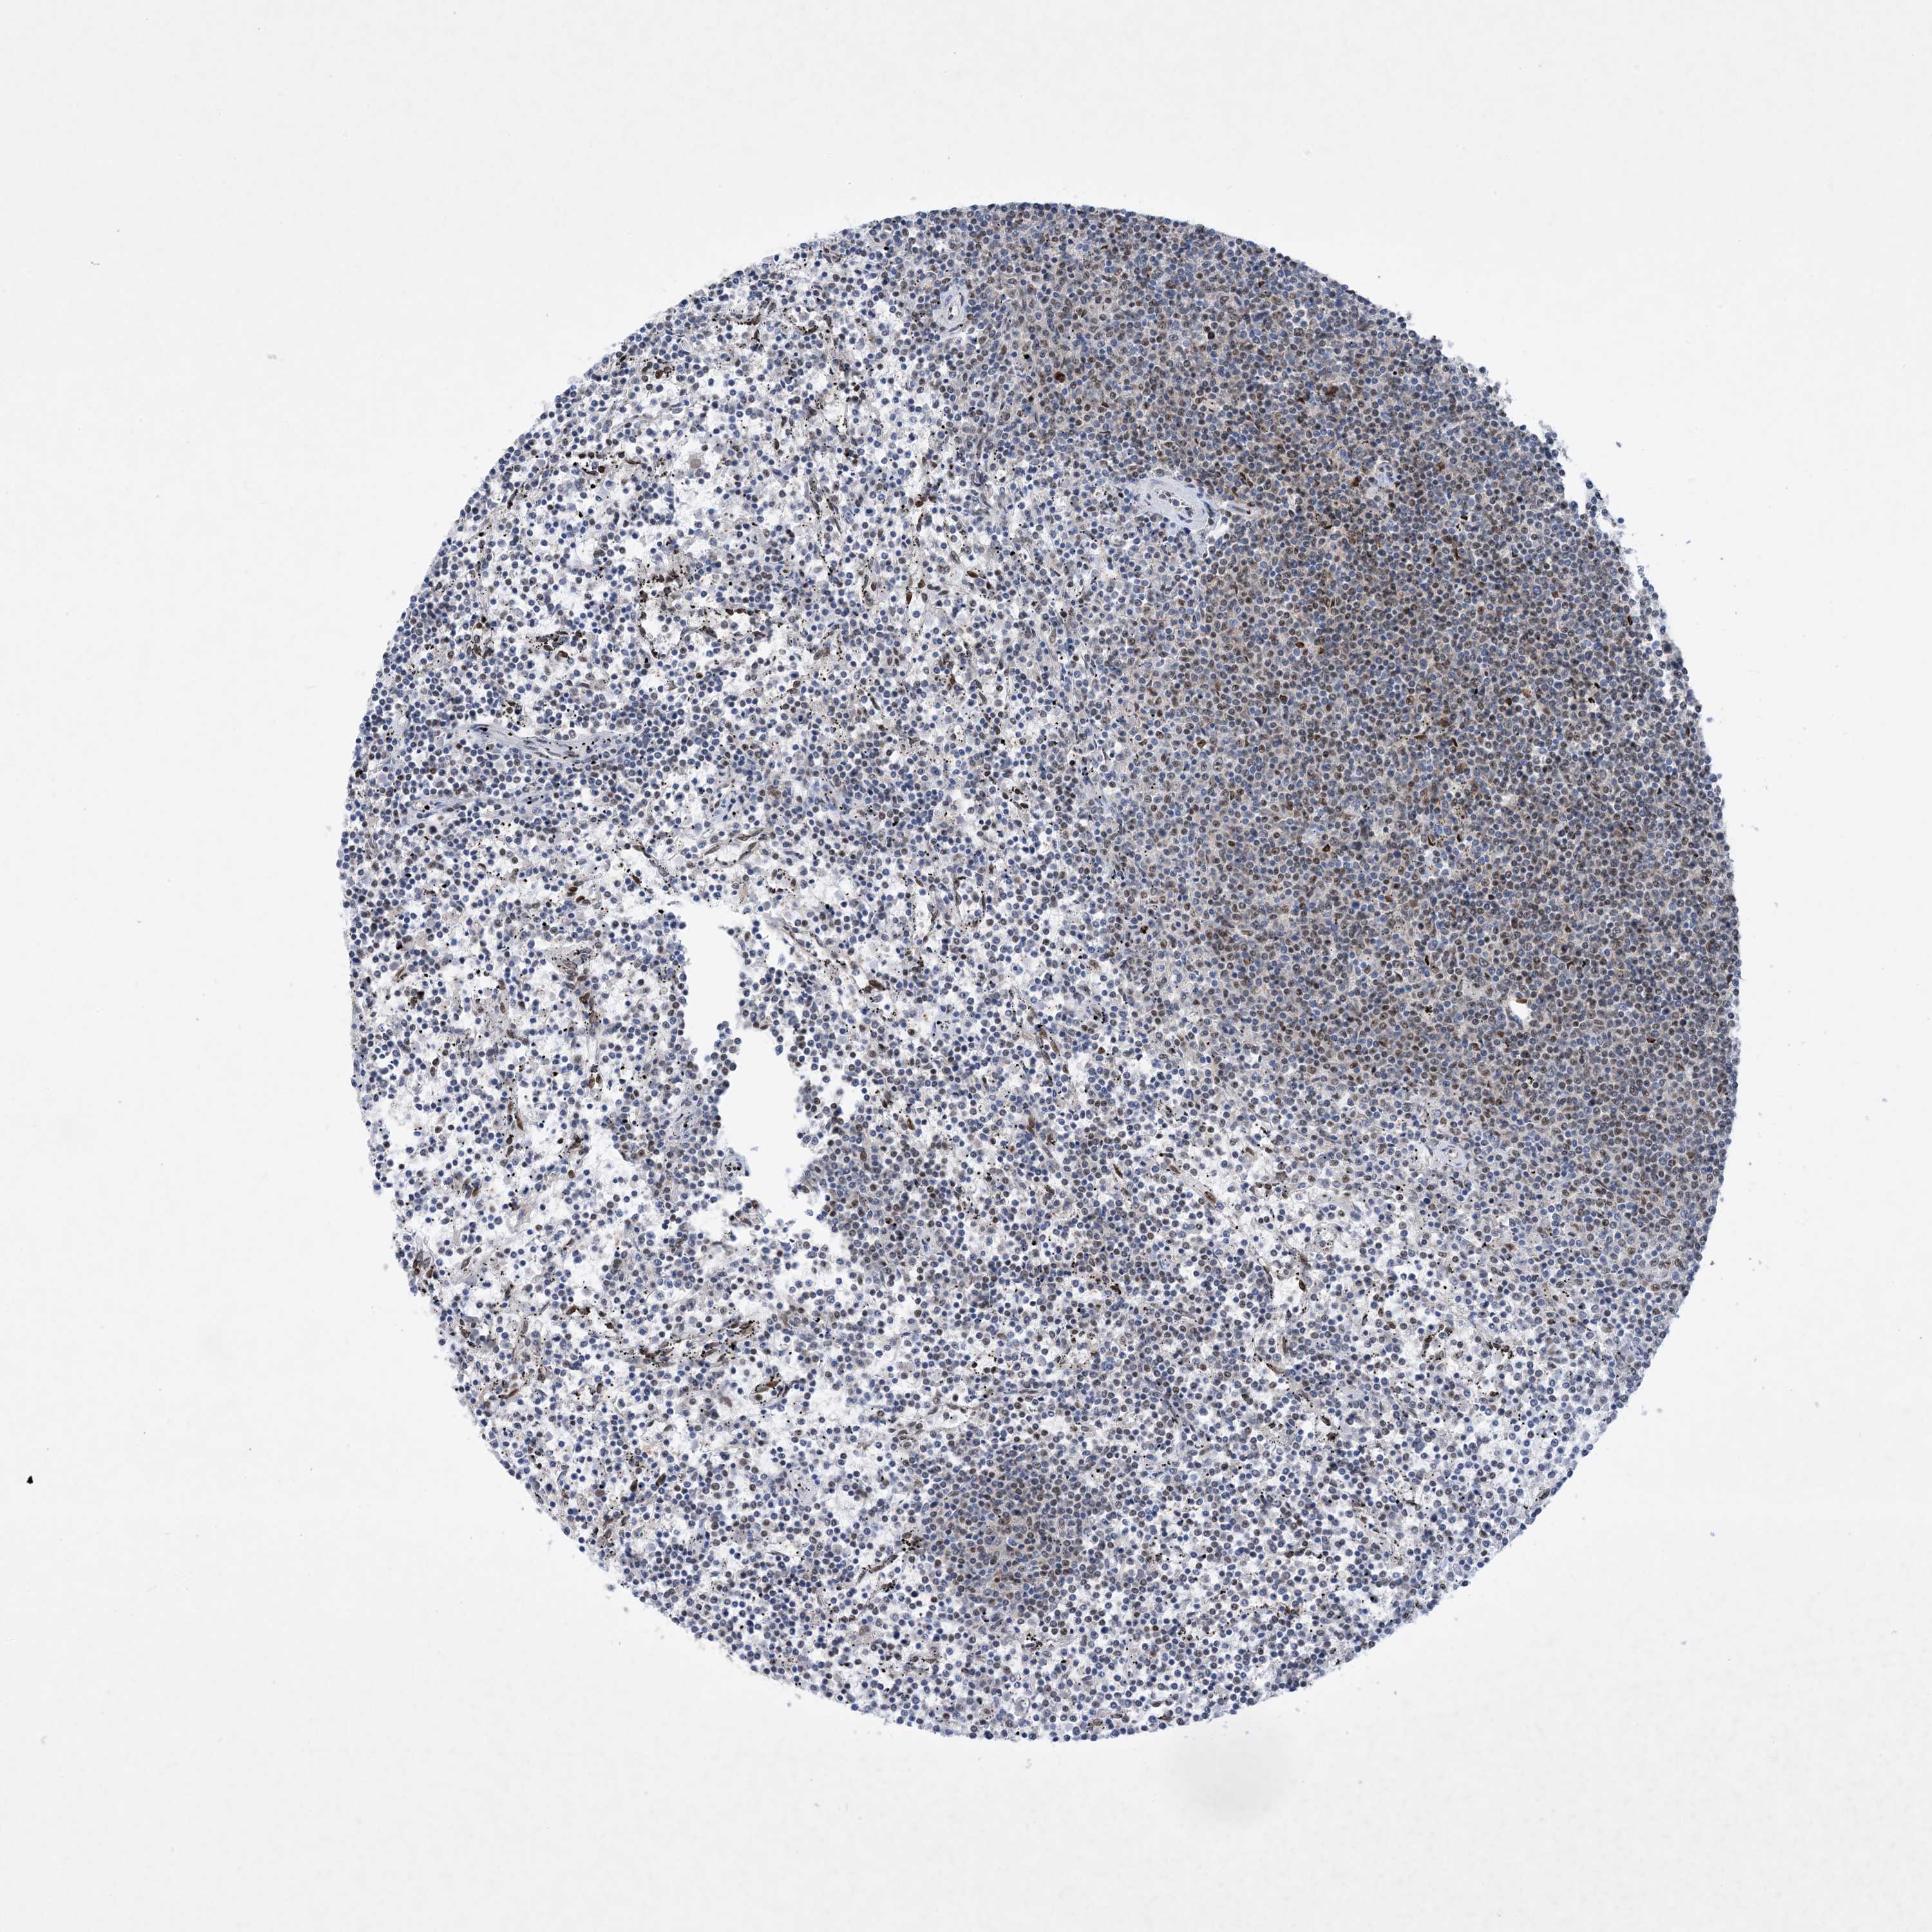

LYMPHOMA - Protein expressioni

A mouse-over function shows sample information and annotation data. Click on an image to view it in a full screen mode. Samples can be filtered based on level of antibody staining by selecting one or several of the following categories: high, medium, low and not detected. The assay and annotation is described here.

Antibody stainingi

Antibody staining in the annotated cell types in the current human tissue is reported as not detected, low, medium, or high, based on conventional immunohistochemistry profiling in selected tissues. This score is based on the combination of the staining intensity and fraction of stained cells.

Each image is clickable and will lead to virtual microscopy that enables deeper exploration of all samples and also displays staining intensity scores, fraction scores and subcellular localization as well as patient and tissue information for each sample.

Antibody HPA031970

Hodgkin's disease, NOS

Malignant lymphoma, non-Hodgkin's type, High grade

Malignant lymphoma, non-Hodgkin's type, Low grade